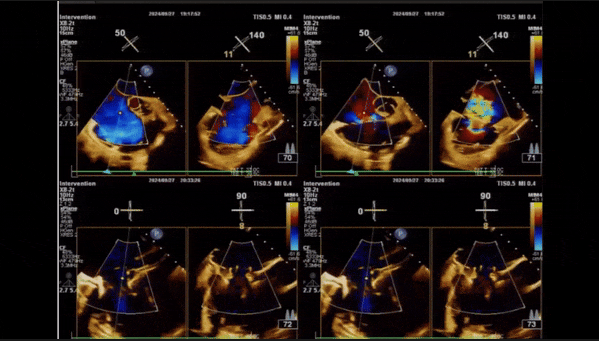

術后即刻返流

術后即刻返流三維

術后即刻經食道超聲可見,三尖瓣假體瓣膜位置合適,牛心包瓣葉運動狀態良好,開閉正常,瓣周及瓣葉對合緣處未見明顯返流,心電圖及心包狀態較術前無明顯變化。

術前術后返流情況對比